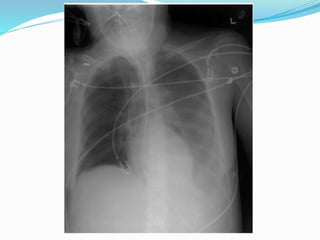

 New CXR infiltrates

CXR - non specific infiltrates